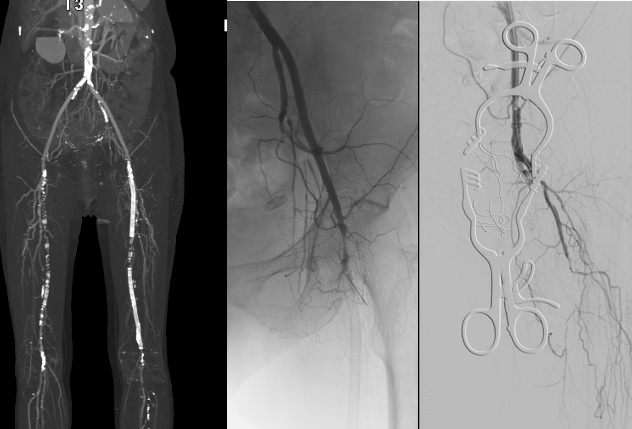

张女士的噩梦始于半年前。因左下肢间歇性跛行伴有疼痛确诊为动脉粥样硬化闭塞症,她在当地医院先后接受了2次下肢动脉球囊扩张及支架手术。然而,介入治疗后只是有1-2个月的短暂缓解,疼痛又是卷土重来,让老人夜不能眠。影像检查显示,她的左股动脉存在长达15厘米的完全闭塞段,且伴有严重的血管钙化。“就像被水泥封死的隧道,导丝根本无法通过。”多次手术失败后,张女士的左足开始出现青紫、皮温降低、足趾坏疽等缺血危象,止痛药逐渐失效,心理防线也随之崩塌。

手术于患者入院后第3天正式开始。术中,介入与血管外科团队沿患者左腹股沟切开8厘米切口,逐层分离至闭塞的股动脉。眼前的景象触目惊心:动脉壁重度钙化,管腔被增生的内膜和暗红色的陈旧血栓完全堵塞。医生们如同考古学家般精细操作——先用血管剪纵向切开动脉,以专用剥离子剥离增厚的内膜,再用取栓导管拉出近远段血管内的条索状血栓。之后通过球囊扩张开通股深动脉,如同在荒漠中开凿出新的灌溉网络,随后血管造影显示血流成功贯通。